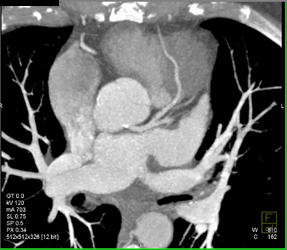

Patent LAD Stent